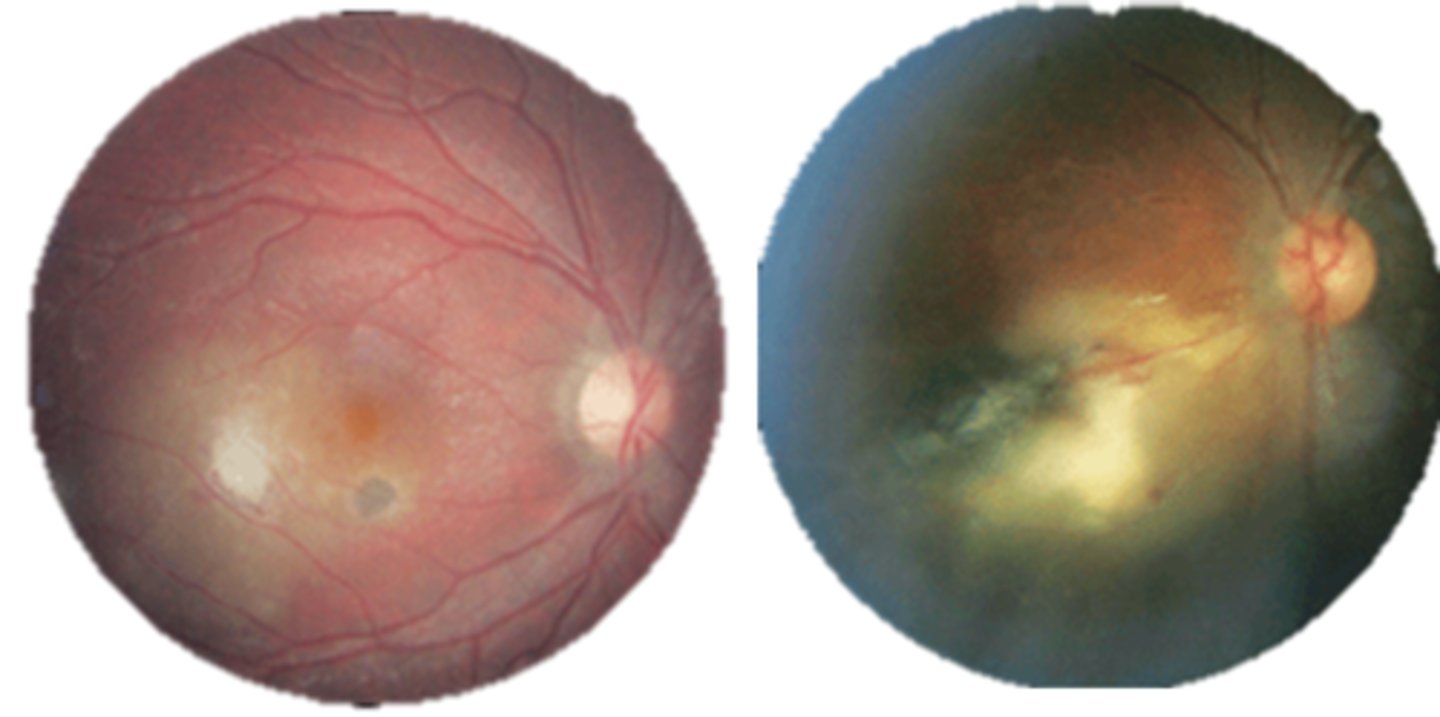

What findings of toxoplasmosis are seen here?

retinal vasculitis

exudative scar

focal, hazy vitritis and retinitis